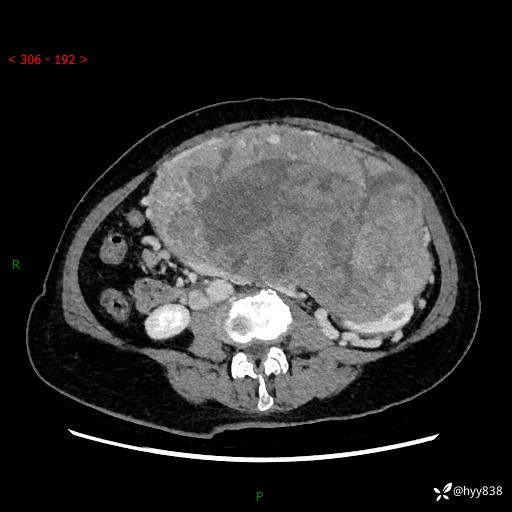

据说只有腹膜后,才能见到如此巨大的肿块---(有结果)

主诉:发现腹膜后占位1周

简要病史:患者1周前因头晕在当地第二人民医院检查发现左侧腹膜后区巨大富血供占位性病变,患者自诉腹部稍硬,无其他不适,无血尿,无腰痛等不适,患者为求进一步治疗来我院,门诊以“腹膜后占位性病变”收入我科。 起病以来,患者精神、饮食、睡眠可,大便正常,小便如上述,体力体重无明显改变。

临床诊断:腹膜后占位

腹部CT增强(动脉期+静脉期 ) ---平扫外院